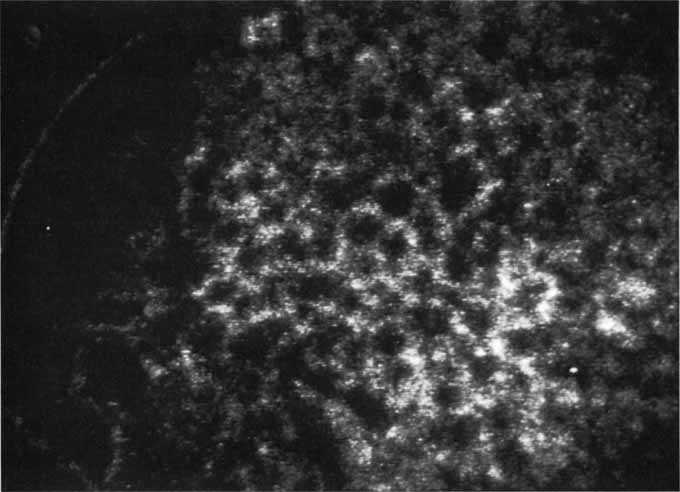

Although initially reported exclusively in middle-aged, black females, PCV has since been recognized as a variant of CNV that can be found in all patients with AMD. This entity is characterized by the presence of an inner choroidal vascular network ending in an aneurysmal bulge clinically seen as a red–orange, spheroid, polyp-like structure. Leakage and bleeding from the choroidal vascular abnormalities result in multiple, recurrent, serosanguinous RPE detachments.25,39,40,41 ICG can be used to identify and characterize the vascular abnormality with high sensitivity and specificity.19–21,40–59 Early-phase images of the lesions show a distinct network of vessels within the choroid. Patients with juxtapapillary involvement show a radial, arching pattern with an inner network of vascular channels extending and connecting with smaller, spanning branches that are more numerous and increasingly prominent at the edge of the PCV lesion.

Larger choroidal vessels in the PCV lesion begin to fill before retinal vessels but appear to fill at a slower rate than the retinal vessels. The lesion initially appears noticeably hypofluorescent relative to the surrounding, uninvolved choroid, but soon after the network is first visible with ICG angiography, small, hyperfluorescent “polyps” can be seen within the choroid. These polypoidal structures correspond to the red–orange choroidal excrescence seen clinically. They leak slowly into the surrounding hypofluorescent area, creating increasing hyperfluorescence. In the late phases of the ICG angiogram, a uniform washout pattern is seen as the dye disappears from the polypoidal vascular structure; the late-staining characteristic of occult CNV is not seen in PCV. PCV may be localized to the macular area without any peripapillary involvement. It may present as a network of small branching vessels ending in polypoidal dilation best-imaged with ICG angiography. (Fig. 12)